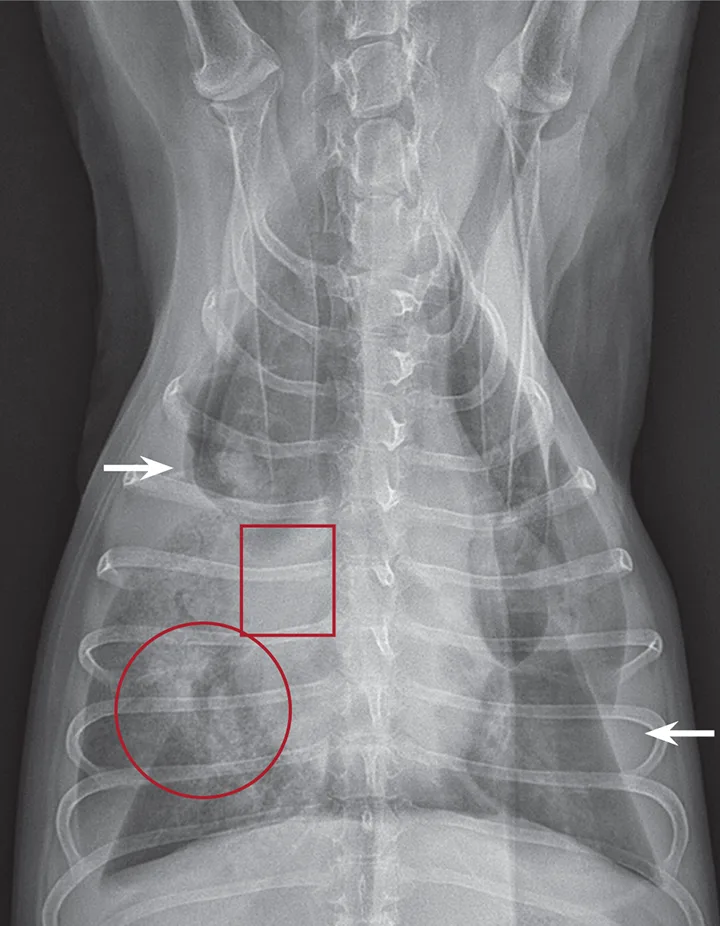

FIGURE 1 Intraoperative image of a congested, torsed lung lobe. Affected lung tissue is often necrotic and friable. Courtesy of Dr. Karen Tobias, University of Tennessee College of Veterinary Medicine

Lung lobe torsion (LLT) occurs when a lung lobe rotates along its long axis, causing constriction of the bronchus and vessels at the hilus (Figure 1). This life-threatening disorder requires immediate surgical intervention.